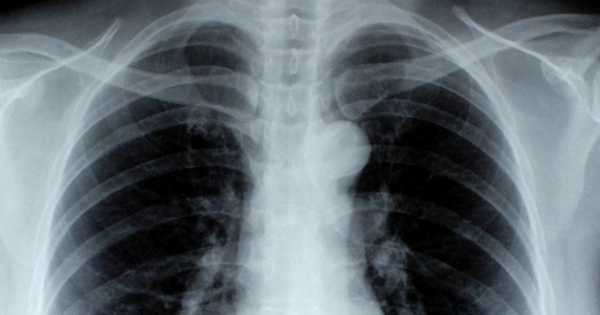

Aunque comer frutas y verduras todos los días está considerado como una acción sana que atrae muchos beneficios a la salud, hasta ahora era algo desconocido que su consumo también ayuda a evitar y combatir la enfermedad pulmonar obstructiva crónica, mejor conocida simplemente como EPOC.

Una reciente investigación, llevada a cabo en Polonia, encontró que consumir diariamente varias frutas y verduras ayuda a los fumadores y a los exfumadores a evitar el desarrollo de una EPOC.

Está comprobado que fumar es el principal factor de riesgo para desarrollar EPOC. Por lo cual, “los profesionales clínicos deben pensar en los beneficios potenciales de una dieta saludable para el fomento de la salud pulmonar, y defender la optimización de la ingesta de frutas y verduras, sobre todo entre los fumadores que son incapaces de dejar de fumar”, expusieron los autores del estudio.

Tras analizar los datos del estudio, los investigadores determinaron que, independientemente de los antecedentes de tabaquismo, aquellas personas que comían 5 o más porciones de ciertas frutas y verduras al día tenían un 35% menos de probabilidades de desarrollar EPOC que los que solo consumían dos porciones al día.

De acuerdo con los investigadores, los antioxidantes encontrados en algunas frutas y verduras pueden tener un rol en la reducción del estrés y la inflamación de los tejidos, que tienen un rol central en el inicio de la EPOC.